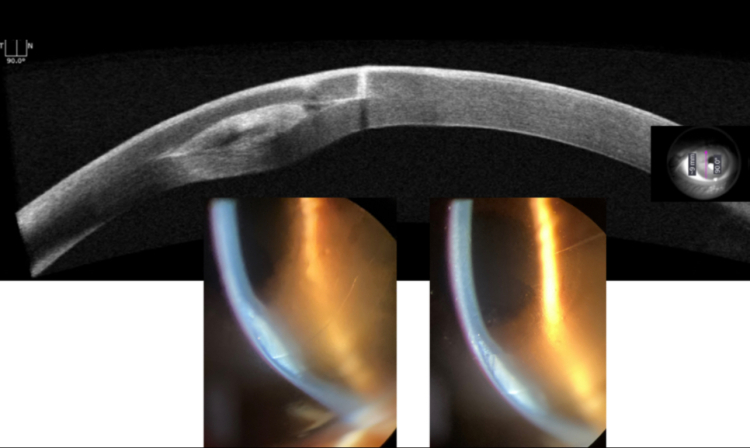

“Bu tedavide hastanın korneasına, doğal kornea dokusundan hazırlanmış halka segmentleri yerleştiriyoruz. Böylece kornea daha düzenli hale geliyor, çıkıntı azalıyor ve hastanın görmesi belirgin şekilde iyileşiyor. İşlem lazer yardımıyla, damla anestezisi altında gerçekleştiriliyor ve hasta aynı gün taburcu edilebiliyor.”